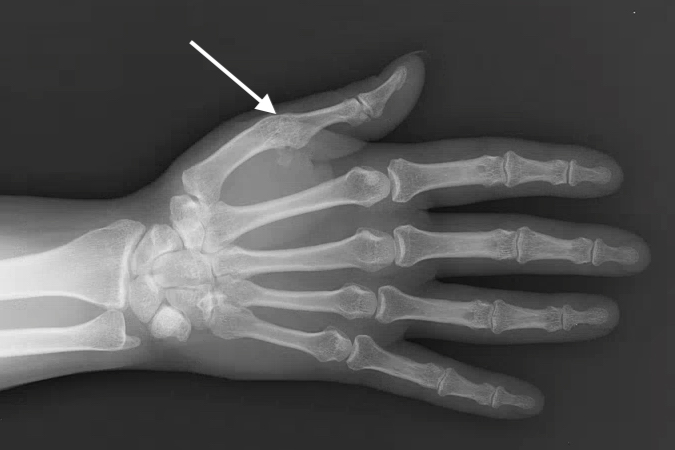

Surgery in Ehlers-Danlos Syndrome patient

• Ten year followup of a thumb MP arthrodesis (arrow) used to treat a hyperextensible MP joint that was causing weak pinch.

Ten year followup of a thumb MP arthrodesis (arrow) used to treat a hyperextensible MP joint that was causing weak pinch.